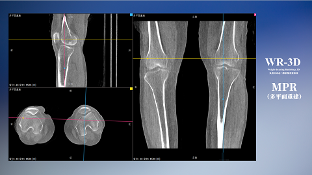

除了西门子之外,国产数字化X线头部厂商安健科技也在负重位三维化技术上创新路径,推出WR-3D技术,通过360度自动旋转扫描装置实现对骨关节的三维扫描,实现在负重位状态下的三维影像成像,解决CT、核磁等无法解决的站立位负重状态下的三维影像信息缺失;WR-3D支持多角度的动态三维摄影观察,能全面的呈现被检查部位在多个角度下三维影像信息,极大的减少了二维负重位检查的漏诊率。对于临床骨科的诊断、运动康复、术后诊断等,具有极高的临床应用价值,得到了国内诸多专家的认可。

(WR-3D技术针对膝关节进行多平面重建)